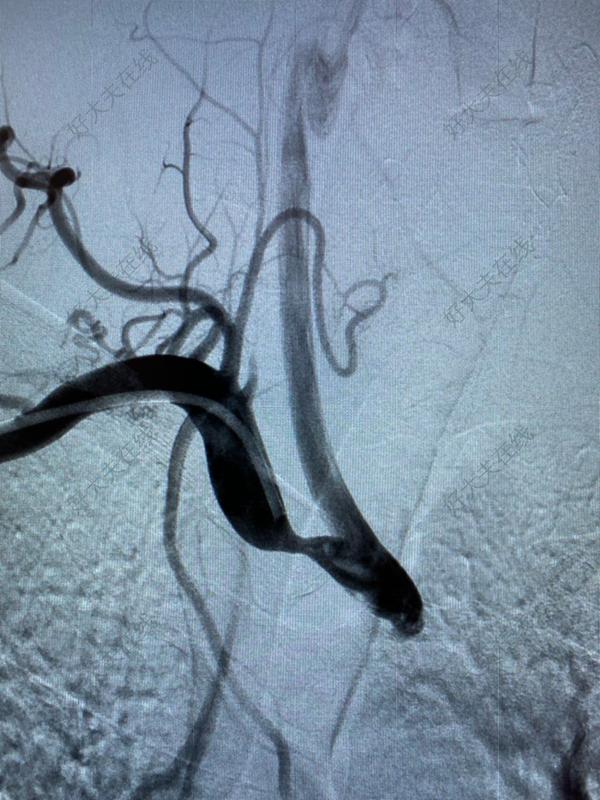

鎖骨下動脈開通支架術(shù)

治療前老年女性,頭暈,走路不穩(wěn),雙上肢血壓差別大于30mmHg,檢查發(fā)現(xiàn)左側(cè)鎖骨下動脈閉塞,椎動脈完全竊血(3期)。鎖骨下動脈閉塞端頭端圓鈍,腔內(nèi)治療開通較困難,但是病人心功能較差,開刀手術(shù)風(fēng)險較高。治療后治療后1月該患者血管閉塞段雖短,但是兩端的頭端都是很圓鈍的形態(tài),鈣化重,而且閉塞部位在血管迂曲移行的位置,在開通過程中,導(dǎo)絲穿出血管的可能性大,手術(shù)潛在風(fēng)險高,術(shù)中采用近遠端雙入路,多角度透視,多種導(dǎo)絲導(dǎo)管小心開通,最終開通成功,恢復(fù)椎動脈正常的正向血供,術(shù)后患者頭暈癥狀緩解,走路不穩(wěn)的癥狀明顯改善。